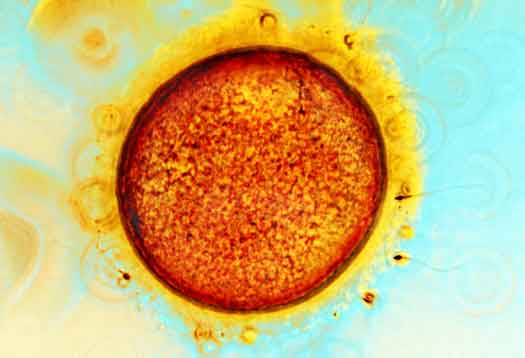

Scoperta la proteina che «prende a calci» gli spermatozoi sterili e risveglia in essi la capacità di fertilizzare un ovulo. La ricerca, pubblicata sulla rivista scientifica Fertiliy and Sterility, è stata condotta da un gruppo di scienziati coordinato da Tony Lai e Karl Swann della Scuola di medicina dell’Università di Cardiff, nel Regno Unito. Gli scienziati hanno rilevato che lo sperma trasferisce in fase di fecondazione una proteina vitale per l’ovulo, conosciuta come PLC-zeta (PLCz). Questa è la chiave che avvia un processo chiamato “attivazione dell’ovulo”, che mette in moto tutti i processi biologici necessari per lo sviluppo di un embrione.

UOMINI STERILI – «Sappiamo che alcuni uomini sono sterili perché il loro sperma non riesce ad attivare gli ovuli – spiega Lai -. Anche se i loro spermatozoi si uniscono all’ovulo, non accade nulla».

Tra le cause, l’eventualità che esso non disponga del corretto funzionamento della PLCz, essenziale per innescare la fase successiva della gravidanza. «Quello che è importante della nostra ricerca è che abbiamo usato una proteina umana, per ottenere dei risultati positivi che avevamo già osservato, ma solo negli esperimenti con i topi». Inoltre i ricercatori hanno scoperto che anche gli ovuli che non si fecondano a causa di un’imperfezione della PLCz, come per alcune forme dell’infertilità maschile, possono essere trattati con la proteina per produrne l’attivazione. «Anche se questo è stato un esperimento di laboratorio e il nostro metodo non poteva essere utilizzato in clinica – conclude Lay -, in futuro si potrebbe produrre la proteina PLCz e utilizzarla per stimolare l’attivazione dell’ovulo in modo del tutto naturale». Secondo i ricercatori, per le coppie che devono utilizzare la fecondazione in vitro, questa tecnica potrebbe aumentare le possibilità di avere un bambino, oltre a contrastare in generale l’infertilità maschile.